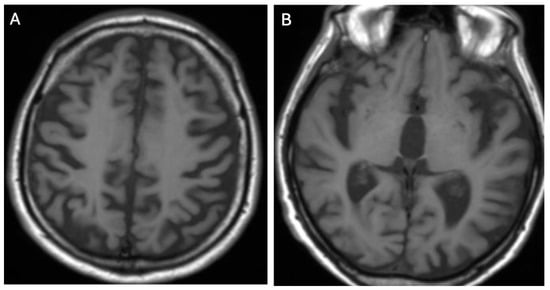

3.1. Classical Brain MRI Examination in WD Patients